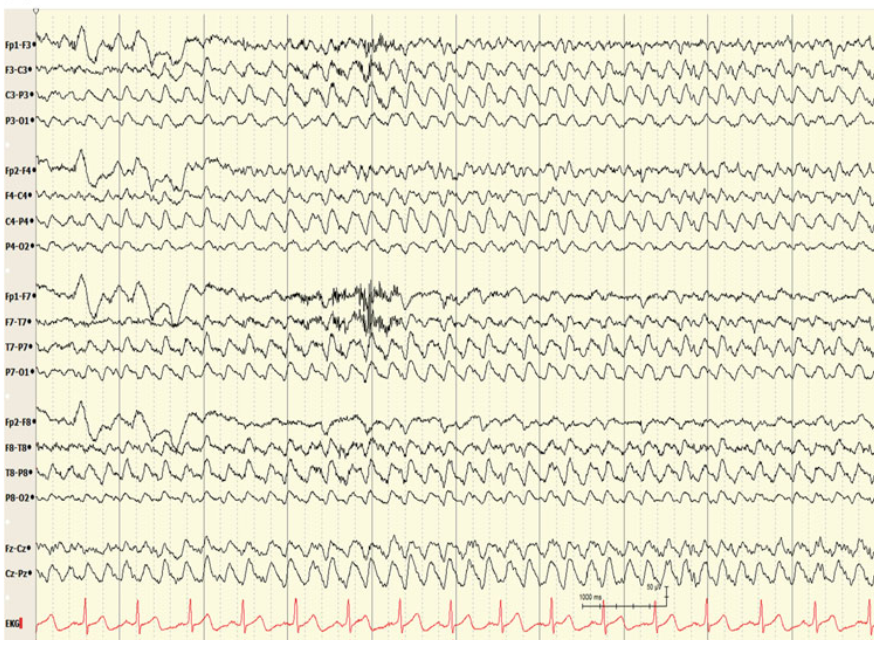

1

Q

A

Electrode pop